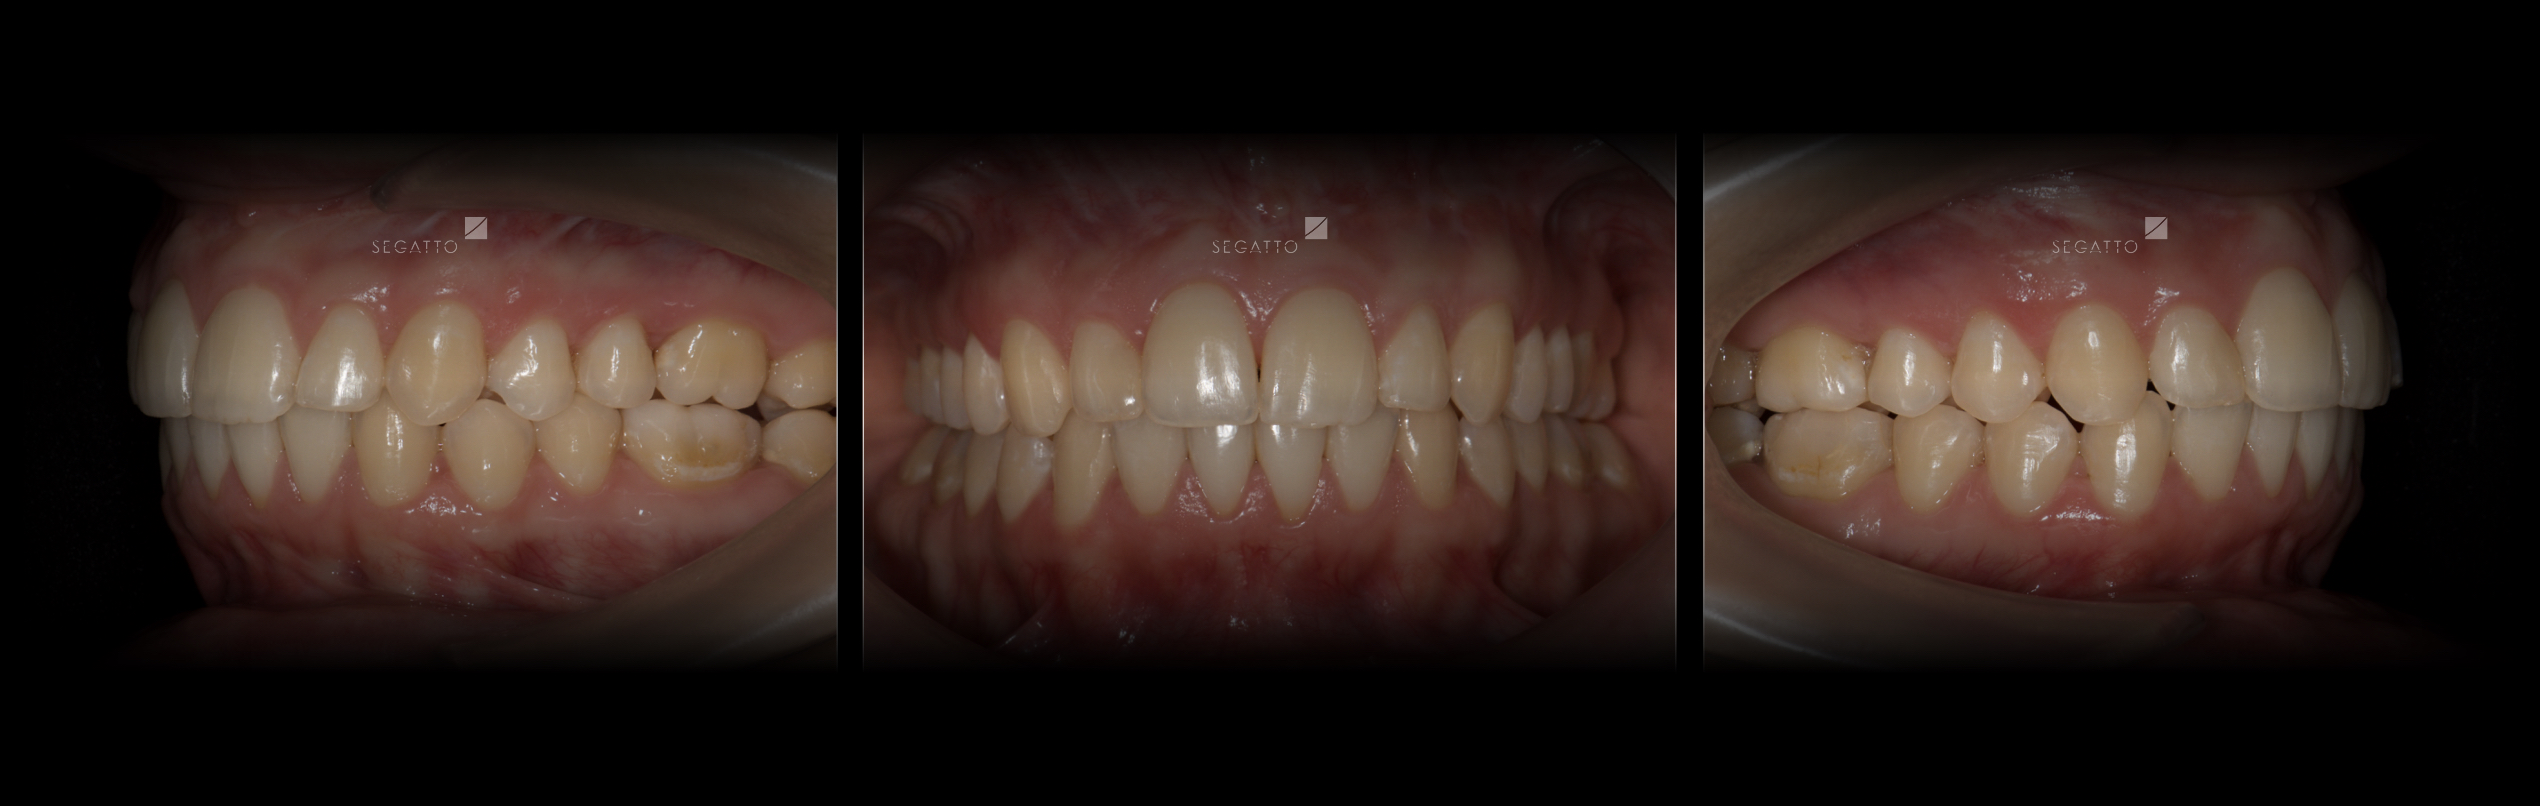

Orthodontics

Cases